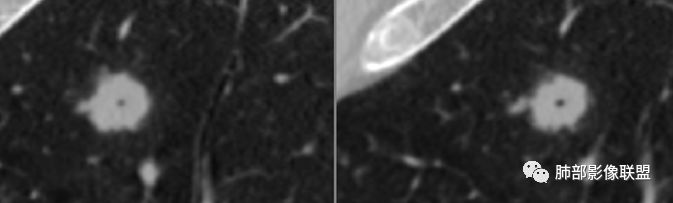

病例2资料

明日の路过:第二例,患者病灶在左肺上叶,分叶、空泡、血管供养征,感觉跟书上的恶性肿瘤图片一模一样。考虑恶性肿瘤可能。建议全身筛查后直接切除。

晨: 第二例,患者病灶在左肺上叶,有分叶、空泡、血管供养征,气管截断,考虑恶性肿瘤,腺癌可能。

王开金江津中心医院呼吸科:病例二,左上叶类圆形结节,分叶,毛刺,血管集束证,空泡,考虑腺癌,鉴别结核球。

欣:第二例:界清结节,有分叶,支气管截断,空泡征,腺癌,IAC

晨读病例二,左肺上叶小结节病灶,有分叶,支气管受阻塞,中断,内可见小泡征,首先考虑恶性病变,腺/鳞癌可能。

波波:第二结节局部膨隆,分叶,空泡,细支气管截断,考虑腺癌。

晨读二:左肺上叶结节,深分叶,支气管堵塞并挤压,内部可见偏心性空泡,考虑恶性,腺癌,早期鳞癌。

大宝儿.蕊:上叶实性结节,边界清,分叶,短毛刺,小泡征,血管集束征,腺癌首先考虑。

南边:

支气管截断。

支气管在门口堵塞恶性居多,结核有时也有。

空泡

分叶

血管纠集

毛刺

总体分析,支持恶性。

应当说两例患者影像学表现都具有比较明显恶性征象,中老年男性患者,均都没有呼吸系统临床症状。

病例2肉瘤样癌的病理意见有些出乎预料,也充分说明病变及影像表现的复杂性。病灶小结节支气管截断、空泡、分叶、短毛刺、血管集束征等似乎均符合肺癌的影像特性。肺鳞癌及肉瘤样癌往往范围较小就可以出现坏死,但如果结节太小则很少能够在影像上观察到坏死区或空洞,没有增强扫描图像更是如此。